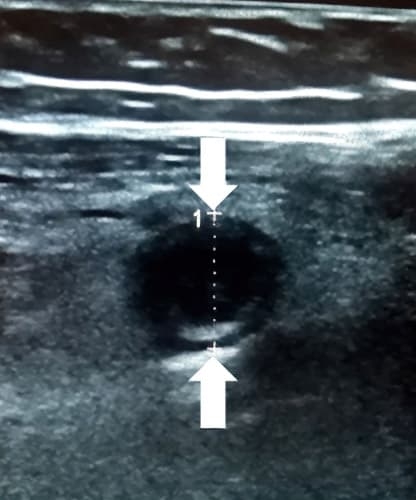

Аппендикс считается расширенным, если под действием компрессии его наружный переднезадний размер, измеренный при поперечном сканировании, более 6 мм (см. рис. 3).

Рисунок 3. Определение диаметра аппендикса.